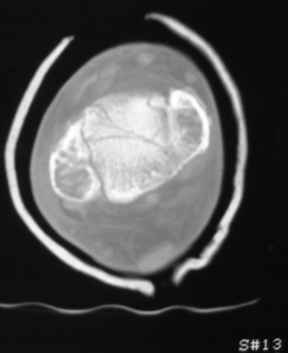

Остеопороз (продолжение 3) - данные КТ

Продолжая тему представляю данные КТ нашей пациентки.